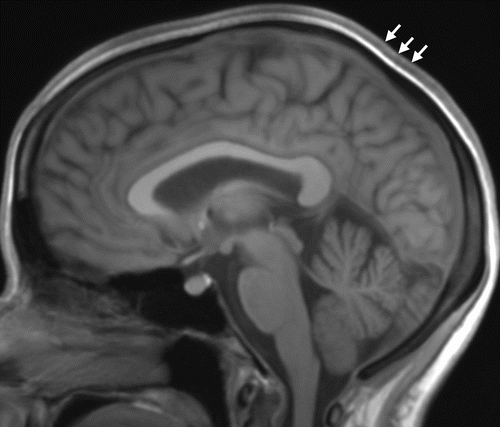

Case History: 28-year-old male presents with history of headaches.